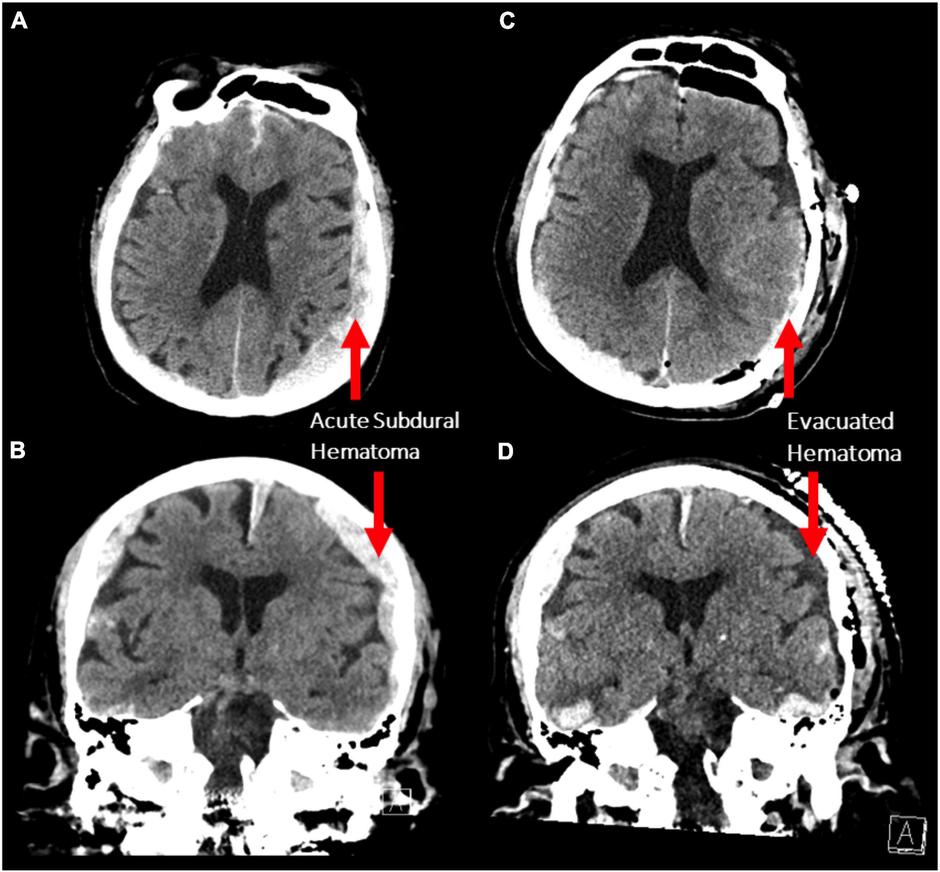

A vi stavljate sliku subduralnog hematoma,koji se javlja kad udarite glavom,ee svašta